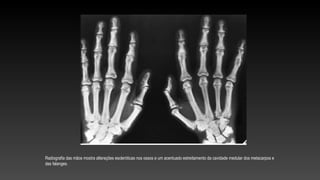

Radiografia das mãos mostra alterações escleróticas nos ossos e um acentuado estreitamento da cavidade medular dos metacarpos e

das falanges.